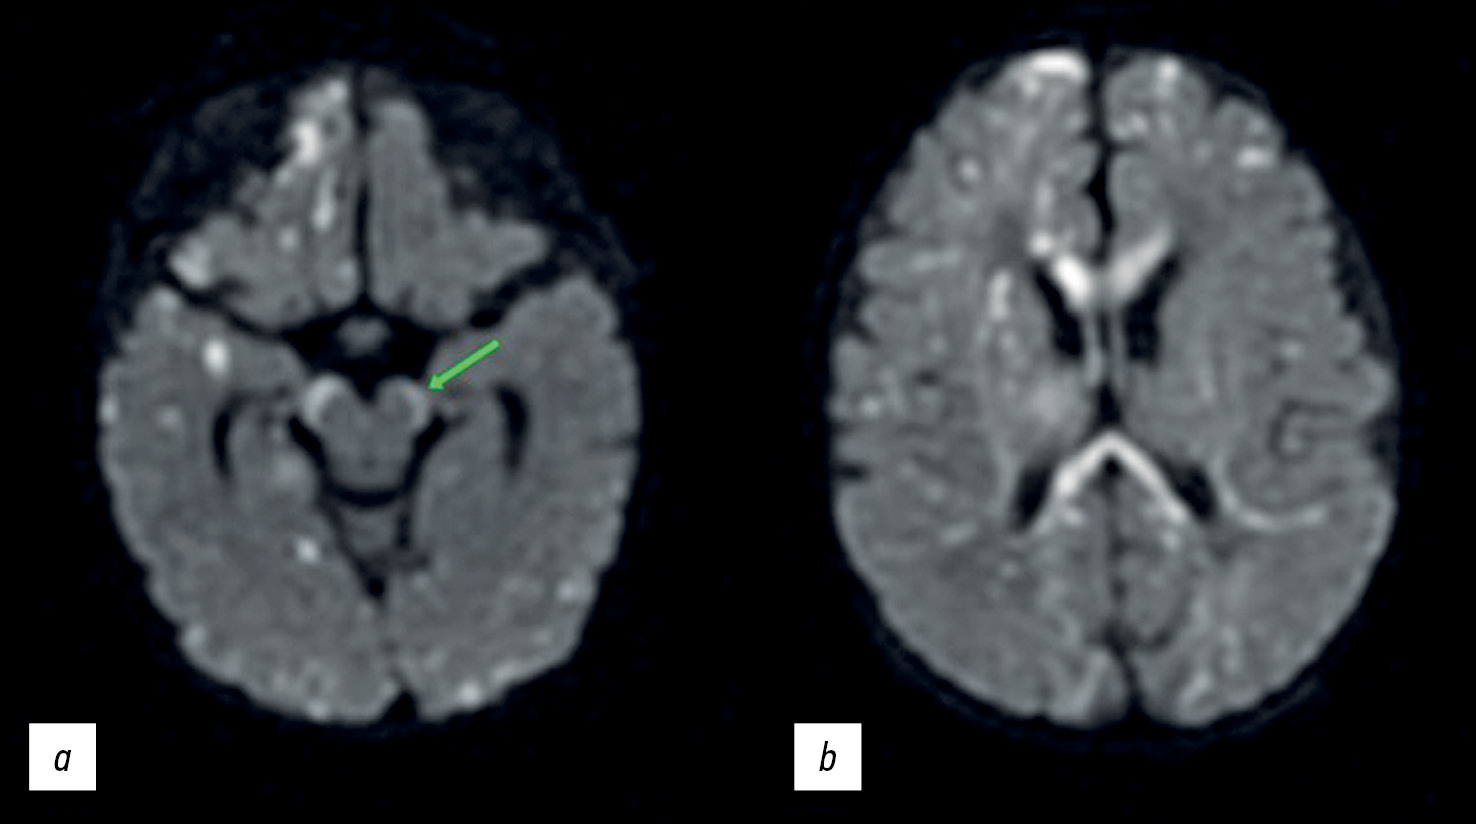

Multiple small (min. 2 mm) restricted diffusion lesions were found in the deep white matter, in and under the cortex, in the corpus callosum, posterior limb of the internal capsule, cerebral peduncles, along the corticospinal tract, and other tracts (Figure 2). Changes in the spinal pathways can be interpreted as either direct injury from incontinentia pigmenti or an early indicator of Wallerian degeneration (pre-Wallerian condition). The latter is characterized by spinal tract injury caused by neuron death and the degradation of the myelin sheath [14]. Small patches of restricted diffusion were regarded as tissue necrosis (infarctions).

Fig. 2. Diffuse-weighted brain images in the axial plane: (a) the arrow shows the hyperintense signal from the spinal tracts in the brain peduncles and (b) multiple lesions and involvement of the corpus callosum.